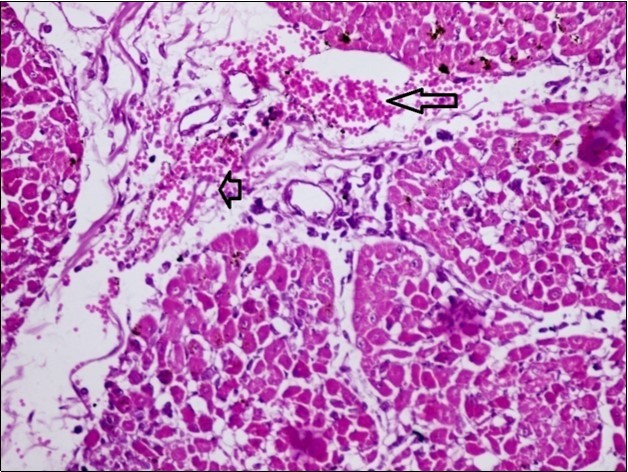

Figures 6.kidneys (dead cattle less than 1 year old) showed severe hydropic degeneration of renal tubular epithelium accompanied by dilated renal tubules, vesicles formations and casts (arrows). (H&E, X 100)

kidneys (dead cattle less than 1 year old) showed severe hydropic degeneration of renal tubular epithelium accompanied by dilated renal tubules, vesicles formations and casts (arrows). (H&E, X 100)

Figures 7.kidneys (dead cattle less than 1 year old) showed severe hydropic degeneration of renal tubular epithelium accompanied by dilated renal tubules, vesicles formations and casts (arrows). (H&E, X 60)

kidneys (dead cattle less than 1 year old) showed severe hydropic degeneration of renal tubular epithelium accompanied by dilated renal tubules, vesicles formations and casts (arrows). (H&E, X 60)